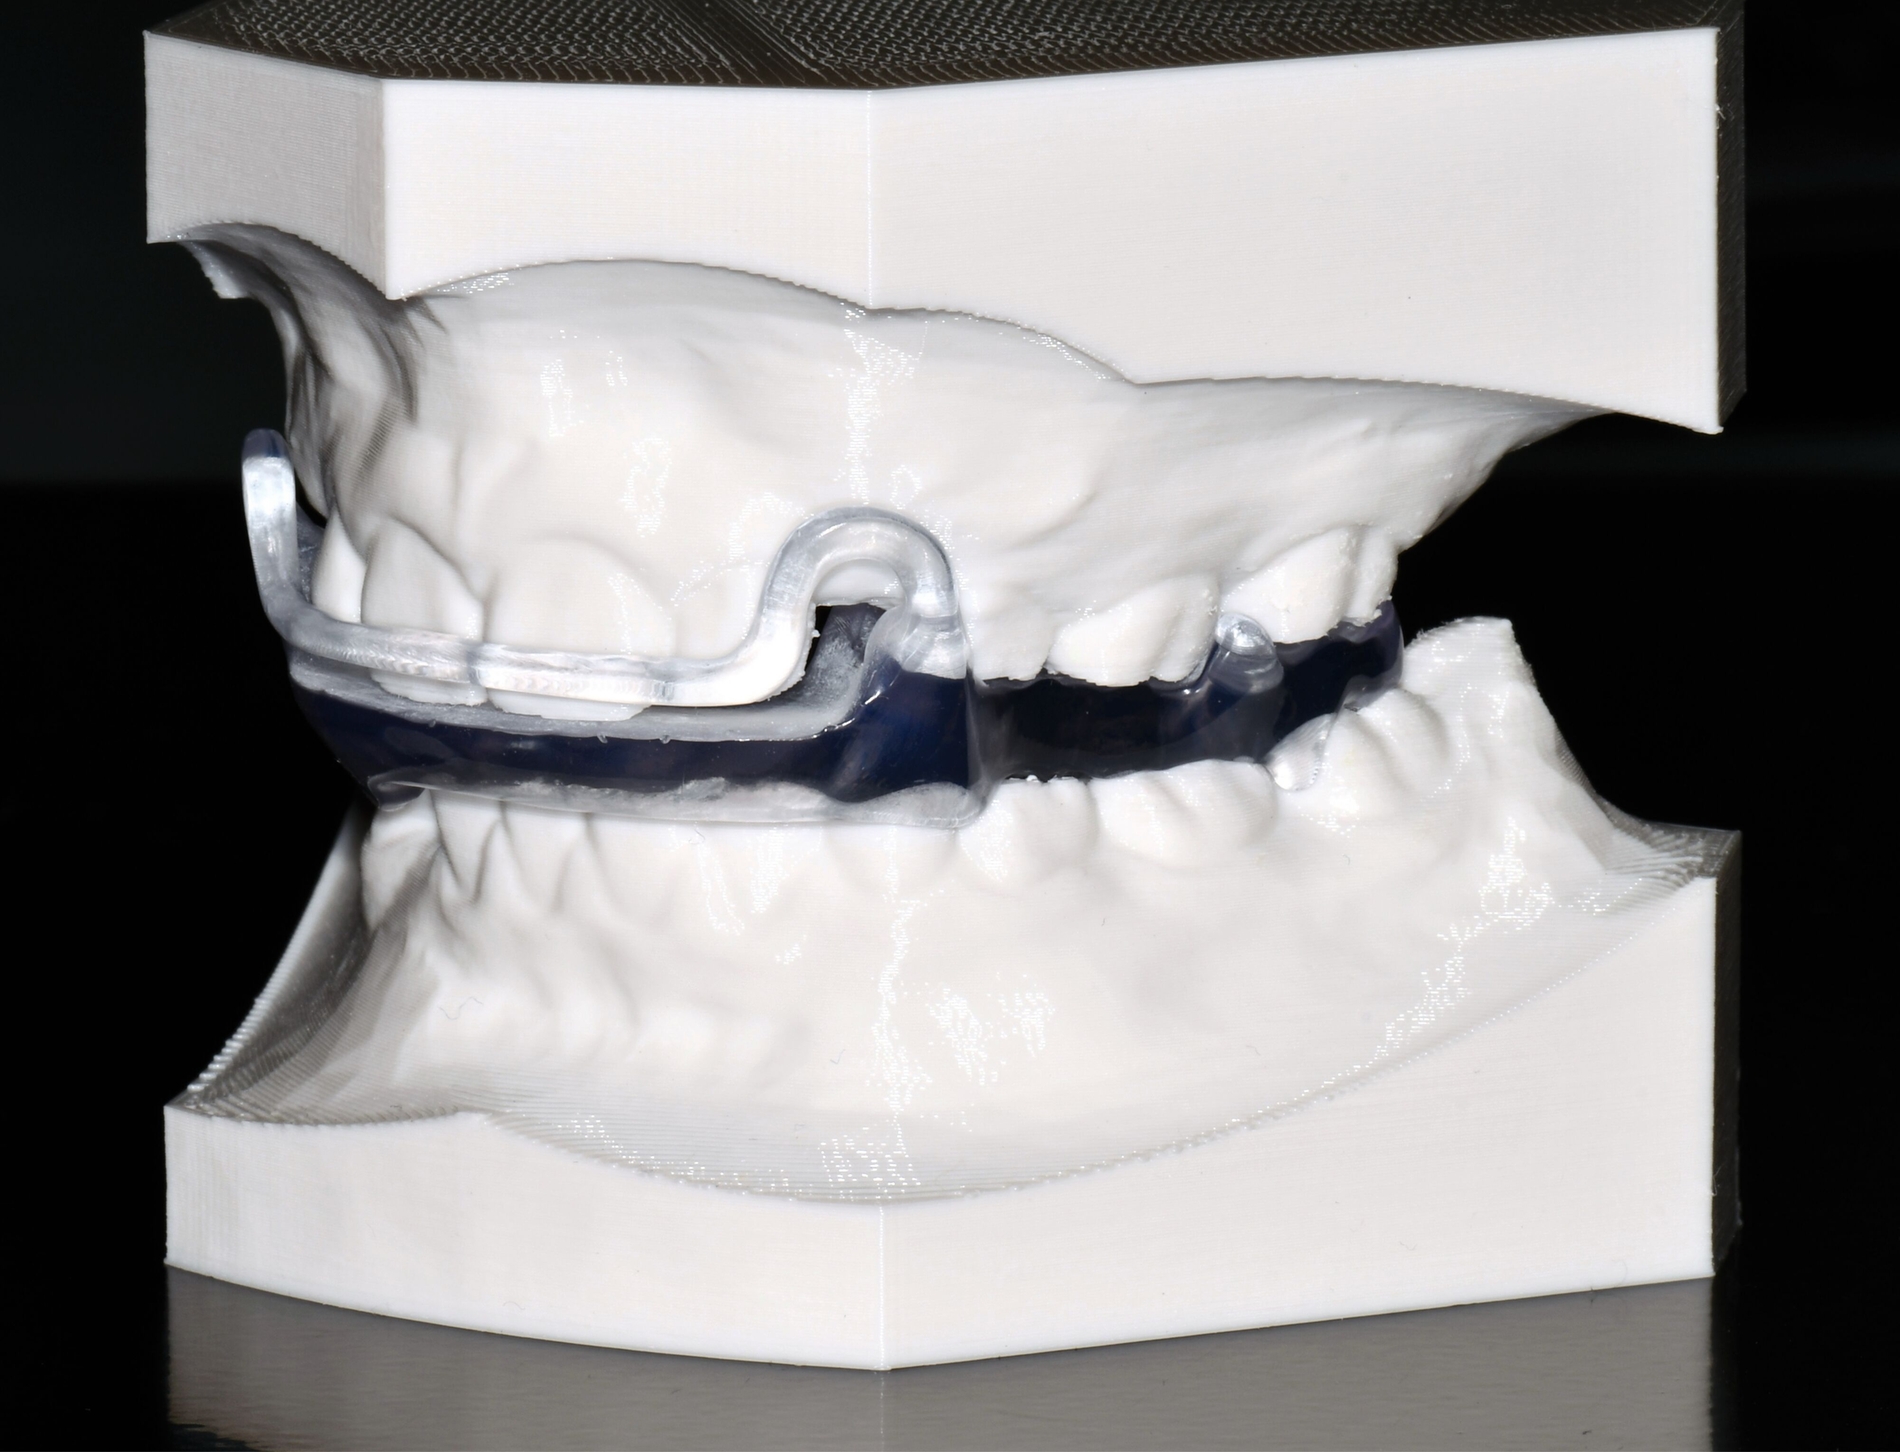

Herausnehmbare Apparaturen

Als hochinnovatives Feld hat sich auch die Herstellung herausnehmbarer Apparaturen im 3-D-Druck entwickelt (Abbildung 4), beschränkt sich jedoch noch auf einzelne Forschungsansätze [Al Mortadi et al., 2012; van der Meer et al., 2016; Graf et al., 2022; Keller et al., 2022]. Intensiv an neuen Konzepten in der Herstellung 3-D-gedruckter herausnehmbarer Apparaturen wird am Universitätsklinikum Heidelberg geforscht. Da herausnehmbare kieferorthopädische Apparaturen im Regelfall bei jungen Patienten eingesetzt werden, kommt dem Vorteil einer unbegrenzten Replikation und einer kostengünstigen und schnelleren Herstellung ein besonderer Stellenwert zu.

Im Unterschied zu konventionellen Apparaturen bestehen die 3-D-gedruckten Apparaturen vollkommen aus Kunststoff. Eine Einarbeitung metallischer Elemente nach dem 3-D-Druck ist möglich [Al Mortadi et al., 2012; Al Mortadi et al., 2024], erfordert jedoch zusätzlichen Zeitaufwand. Zur Herstellung herausnehmbarer Apparaturen eignen sich konventionelle praxisinterne 3-D-Stereolithografie-Drucker, die in vielen Fällen bereits im regulären Praxisalltag zum Modelldruck verwendet werden. Die verwendeten Kunststoffe sollten dabei eine Klasse-IIa-Zertifizierung aufweisen, so dass ein sicherer langfristiger intraoraler Einsatz der Apparatur gewährleistet ist. Weiter muss die Apparatur nach dem 3-D-Druck gemäß den Herstellerangaben nachprozessiert werden. Im Regelfall beinhaltet dieser Prozess ein Waschen in Isopropylalkohol (IPA) sowie eine Nachhärtung im Lichthärtegerät. Eigens durchgeführte Studien sowie die bisherige klinische Erfahrung bestätigen eine hohe mechanische Stabilität, eine hohe Passgenauigkeit sowie eine breite Akzeptanz der Patienten [Roser et al., 2021; Roser et al., 2023; Segnini et al., 2023]. Des Weiteren wecken die 3-D-gedruckten Apparaturen bei den meist jungen Patienten großes Interesse, was wiederum die Trage-Compliance unterstützt. Durch weitere Entwicklungen im 3-D-Druckbereich wird zukünftig auch ein Farbdruck möglich werden.